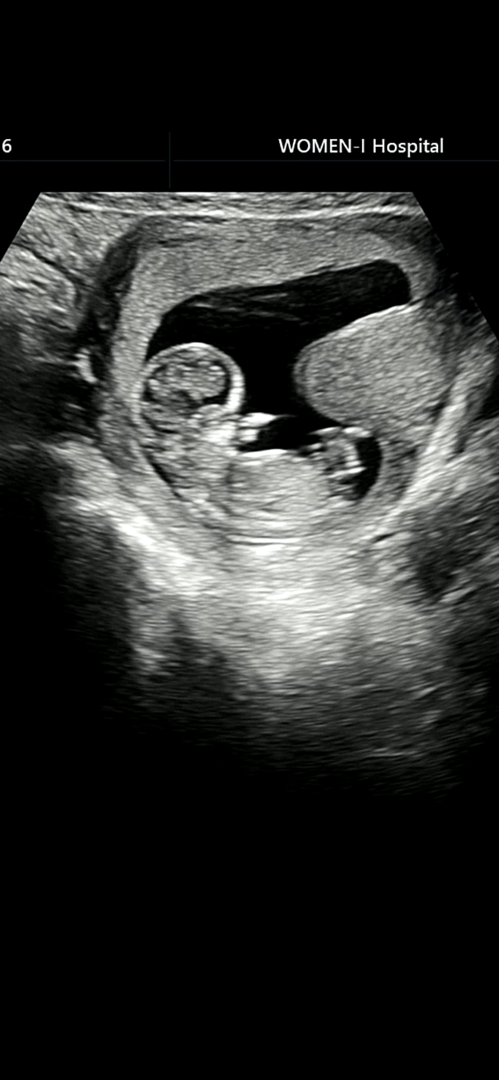

각도법이 봐질까요 ㅠㅠ??

사진이 애매해서 각도법 보는게 가능한진 모르겠어요 ㅠㅠ 이 사진으로 가능할까요? 도와주세요

아들같은데요?